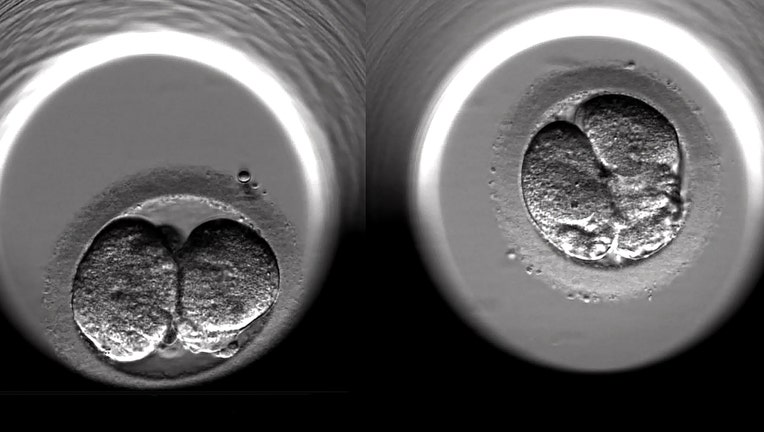

This undated screen grab shows the cell-division of two fertilized human embryos during the first 24 hours of embryonic development following IVF treatment at a private clinic in London. (Jim Dyson/Getty Images)